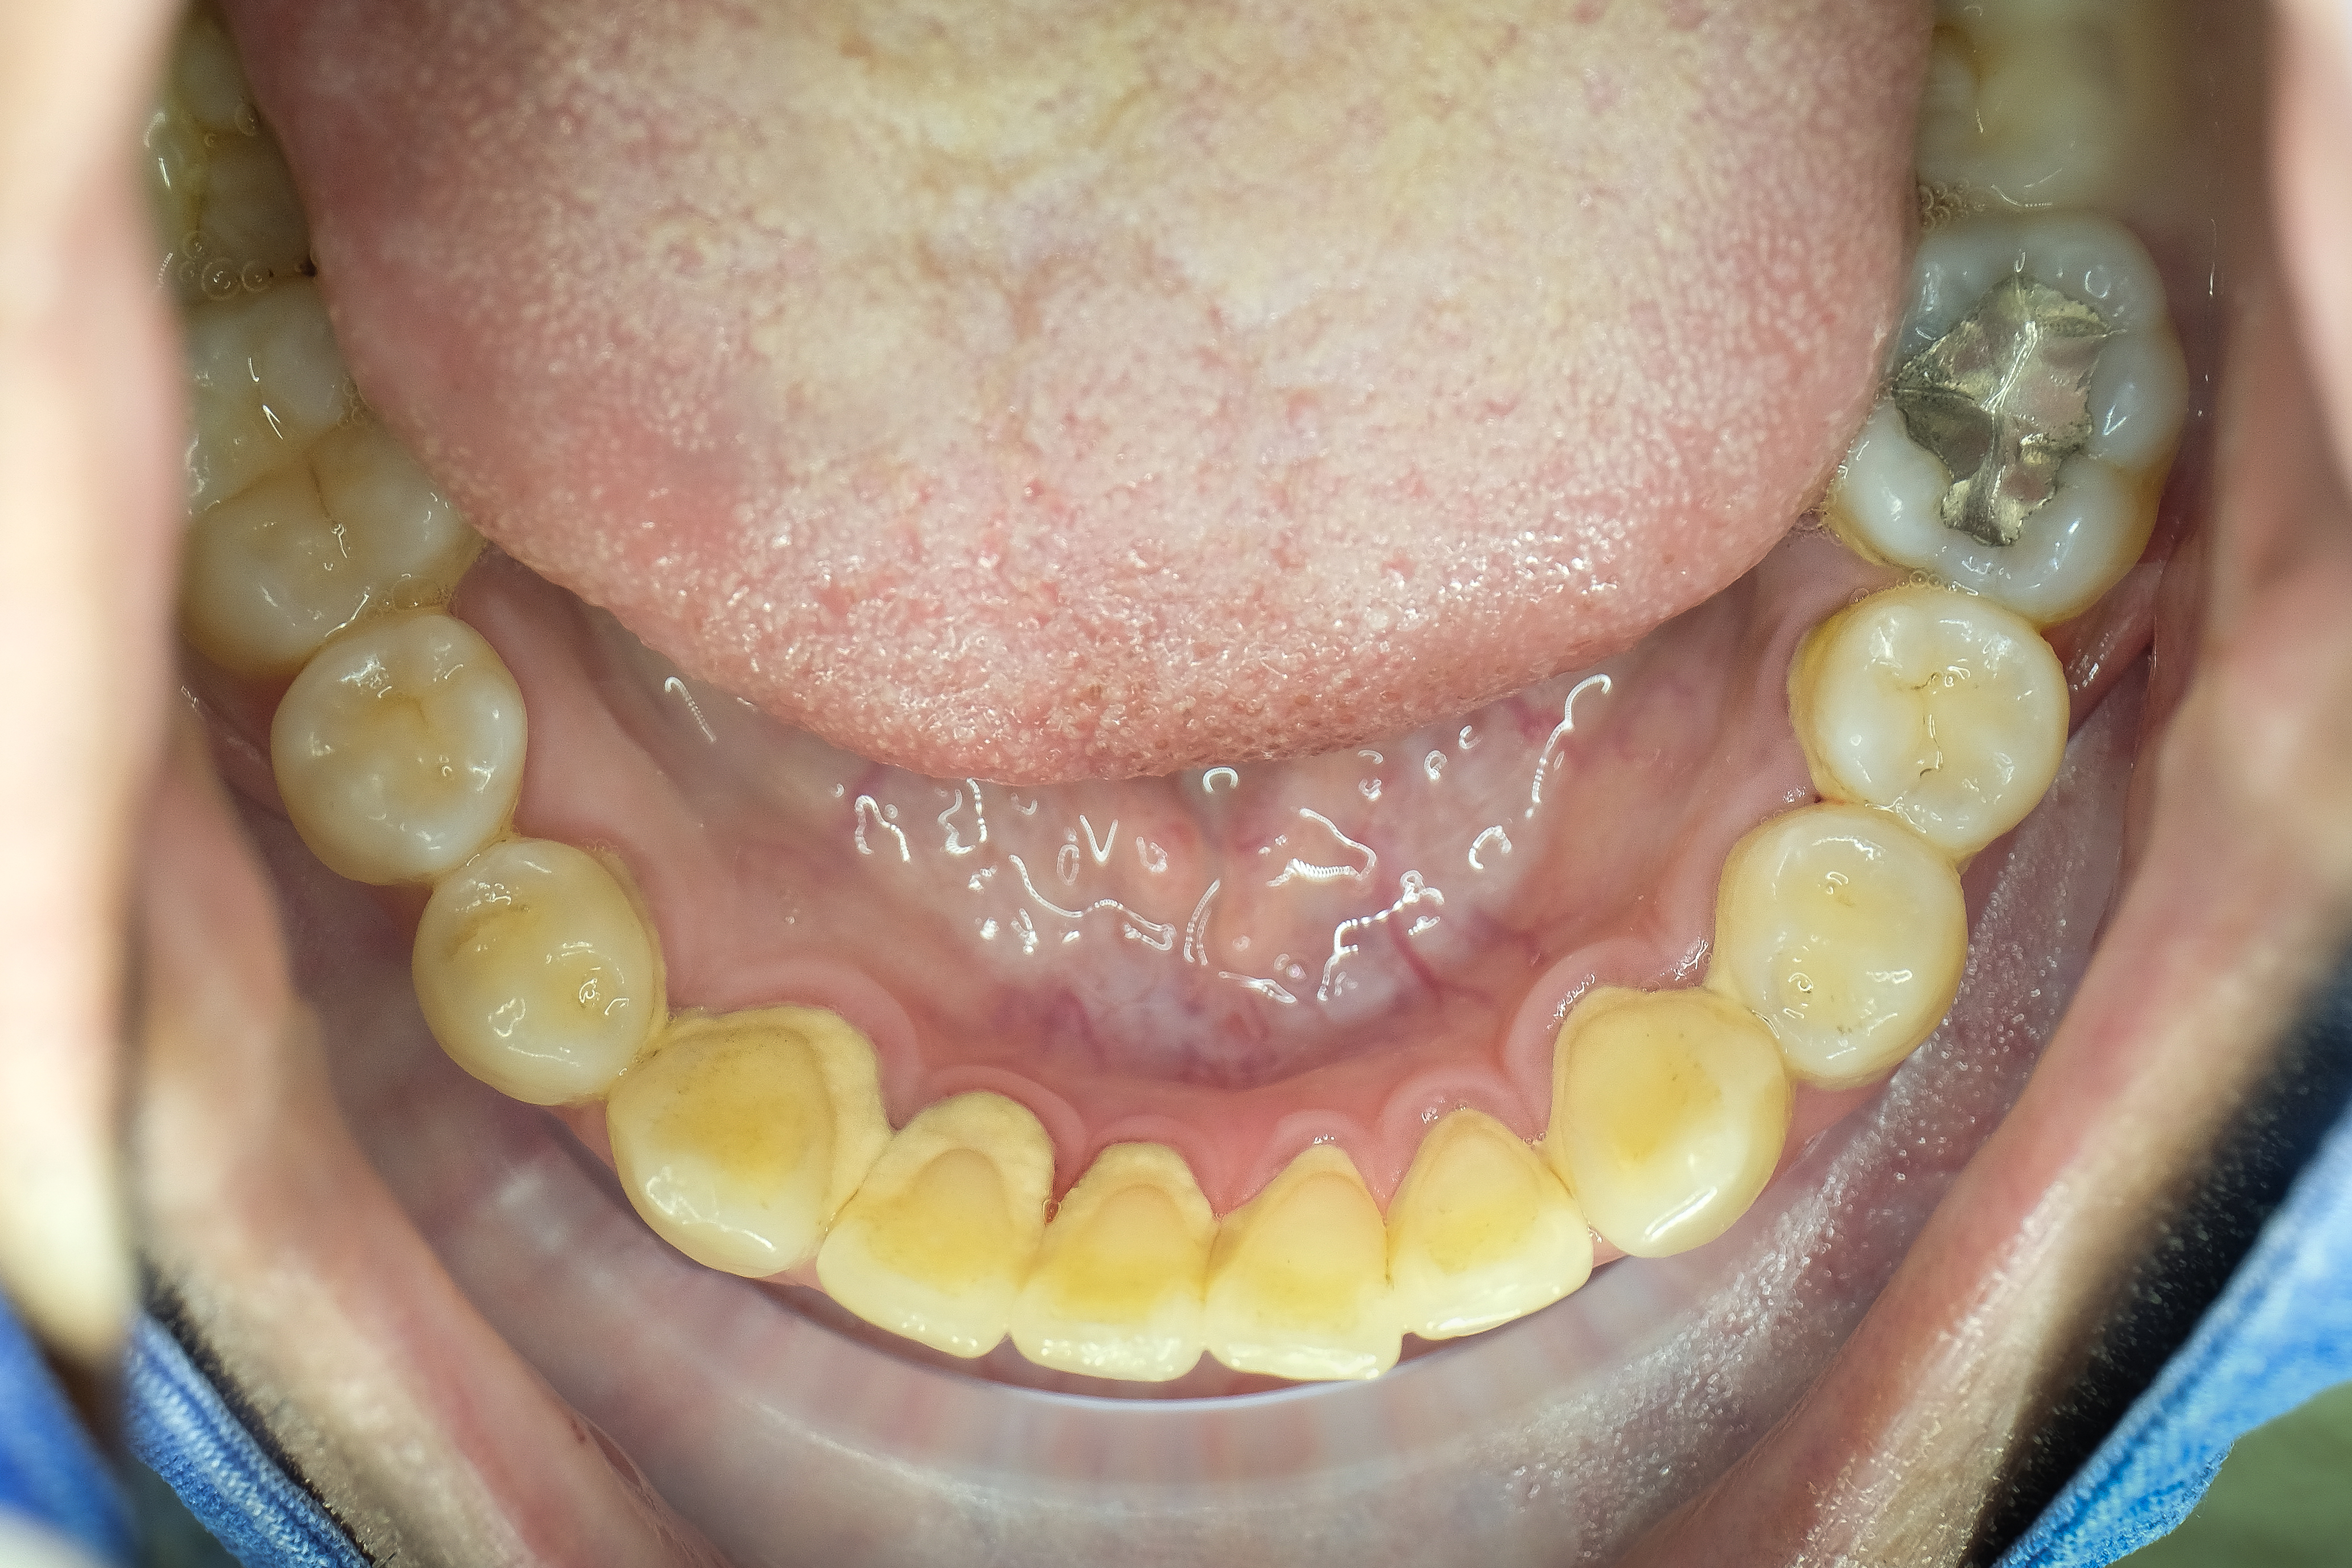

スケーリング前,後写真

だからなのか、スケーリングをしてから何日か後に

「歯茎が崩れ落ちた、歯がしびれる」

「スケーリングが歯茎をダメにしたのではないのか」という方もたまにあります。

しかし、これは違いますね!

通常のようで定常ではない状況から取り出し本当の定常に戻った!ということだと考えればいいわけです。